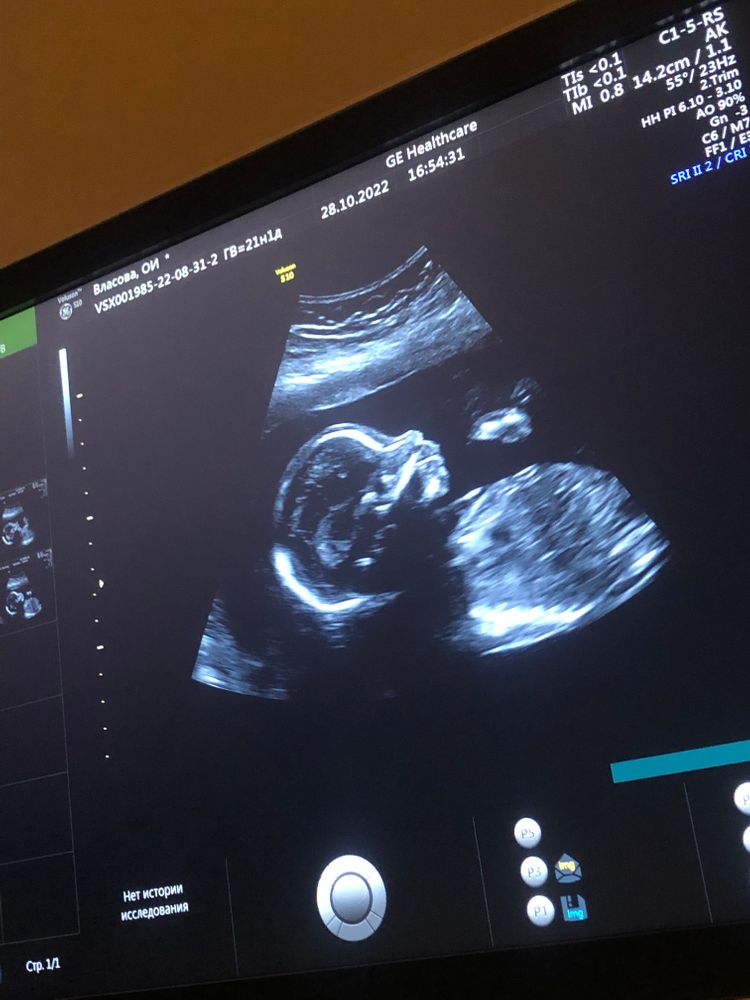

2 скрининг, поход на узи, попытка 3

УЗИ, КТГ, доплерНу что, опять мы не все дали посмотреть узисту. Осталось сердце посмотреть. Записали на 1 ноября😁, попытка номер 4. Показываемся частями.

В этот раз показал нам личико, сделали даже 3Д фото. Такие мы уже большие😍 мальчишки с пухлыми губами😁 (срок 20 недель и 1 день, по узи 21 неделя и 1 день)